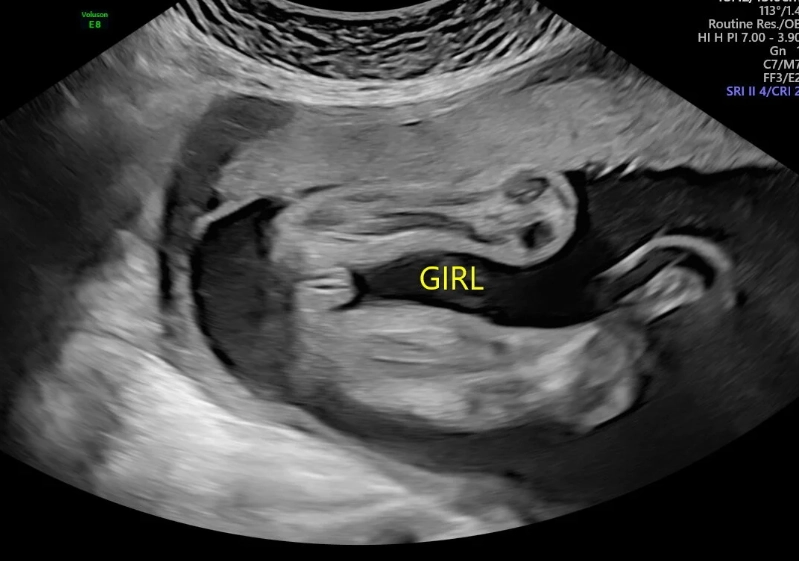

This is the week synonymous with the "dating scan" or "nuchal translucency (NT) scan." It's a pivotal appointment. Here’s what they’re really looking for, beyond just giving you a cute picture:

- Accurate Dating: Measuring the baby's length (Crown-Rump Length) to confirm or adjust your due date. This is the most accurate time to do it.

- Nuchal Translucency Measurement: This ultrasound measures the fluid at the back of the baby's neck. An increased measurement can be a soft marker for certain chromosomal conditions, like Down syndrome.

- Early Anatomy Check: The sonographer will check for the presence of major structures—the brain, stomach, bladder, spine, and the four chambers of the heart.

- Multiple Pregnancy: Confirming whether you're carrying one baby or more.

This scan is often combined with a blood test (the first part of the combined screening or NIPT) to assess risk. It's a screening test, not a diagnosis. A "high-risk" result simply means further diagnostic testing (like CVS or amniocentesis) is offered. The emotional weight of this scan is huge. It’s normal to feel anxious beforehand.